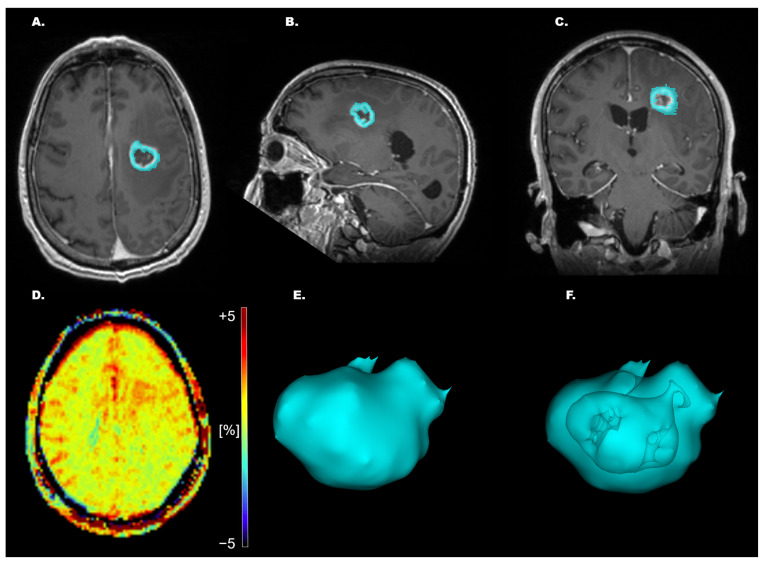

Objectives: To assess amide proton transfer weighted (APTw) MR imaging capabilities in differentiating high-grade glial tumors across alpha-thalassemia/mental retardation X-linked (ATRX) expression, tumor-suppressor protein p53 expression (p53), O6-methylguanine-DNA methyltransferase promoter (MGMTp) methylation, isocitrate dehydrogenase (IDH) status, and proliferation marker Ki-67 (Ki-67 index) as a preoperative diagnostic aid. Material & Methods: A total of 42 high-grade glioma WHO grade 4 (HGG) patients were evaluated prospectively (30 males and 12 females). All patients were examined using conventional MRI, including the following: T1w-MPRAGE pre- and post-contrast administration, conventional T2w and 3D FLAIR, and APTw imaging with a 3T MR scanner. Receiver operating characteristic (ROC) curves were calculated for the APTw% mean, median, and max signal for the different molecular biomarkers. A logistic regression model was constructed for combined mean and median APTw% signals for p53 expression. Results: The whole-tumor max APTw% signal could significantly differentiate MGMTp from non-MGMTp HGG, p = 0.035. A cutoff of 4.28% max APTw% signal yielded AUC (area under the curve) = 0.702, with 70.6% sensitivity and 66.7% specificity. The mean/median APTw% signals differed significantly in p53 normal versus p53-overexpressed HGG s: 1.81%/1.83% vs. 1.15%/1.18%, p = 0.002/0.006, respectively. Cutoffs of 1.25%/1.33% for the mean/median APTw% signals yielded AUCs of 0.786/0.757, sensitivities of 76.9%/76.9%, and specificities of 50%/66.2%, p = 0.002/0.006, respectively. A logistic regression model with a combined mean and median APTw% signal for p53 status yielded an AUC = 0.788 and 76.9% sensitivity and 66.2% specificity. ATRX-, IDH- wild type (wt) vs. mutation (mut), and the level of Ki-67 did not differ significantly, but trends were found: IDH-wt and low Ki-67 showed higher mean/median/max APTw% signals vs. IDH-mut and high Ki-67, respectively. ATRX-wt vs. mutation showed higher mean and median APTw% signals but lower max APTw% signal. Conclusions: APTw imaging can potentially be a useful marker for the stratification of p53 expression and MGMT status in high-grade glioma in the preoperative setting and potentially aid surgical decision-making.